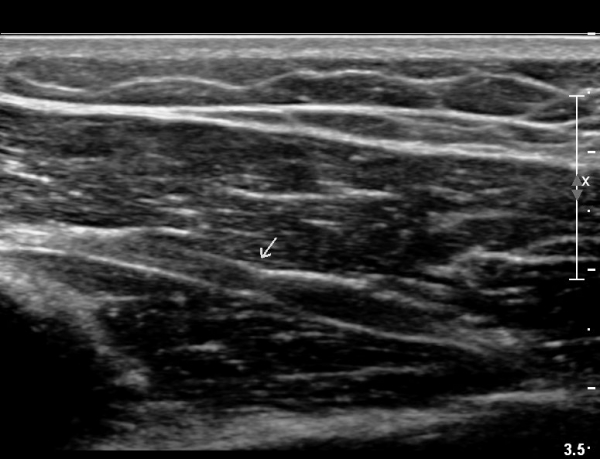

ÃÊÀ½ÆÄ°Ë»ç

¿ä°ñ °í¶û¿¡¼ ¿ä°ñ½Å°æ Ⱦ´Ü¸é°Ë»ç»ó ¿ä°ñ½Å°æÀÇ °æ¹ÌÇÑ Àú¿¡ÄÚ ºÎÁ¾ÀÌ °üÂûµÈ´Ù(»çÁø 2).

ŽÃËÀÚ¸¦ Á¶±Ý ¸»´ÜÀ¸·Î À̵¿ÇÏ´Ï ¿ä°ñ½Å°æ Àú¿¡ÄÚ ºÎÁ¾ÀÌ ´õ¿í ¶Ñ·ÈÇѵ¥(»çÁø 2),